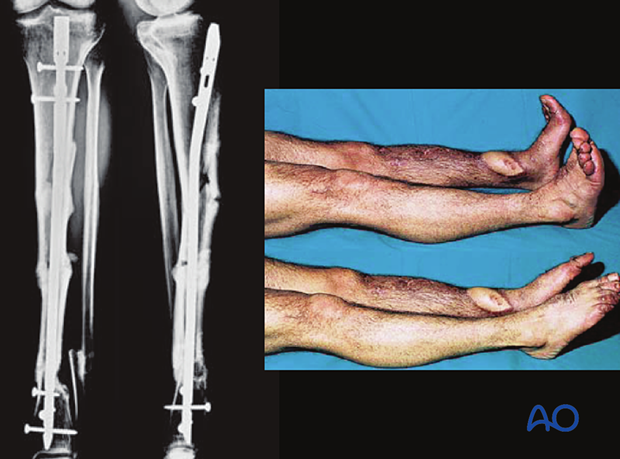

Intramedullary (IM) nailing can be chosen to manage open, complex fractures of the tibia. These images show a severe open segmental tibial fracture, in which IM nailing was performed.

These images show the healed tibial fracture.